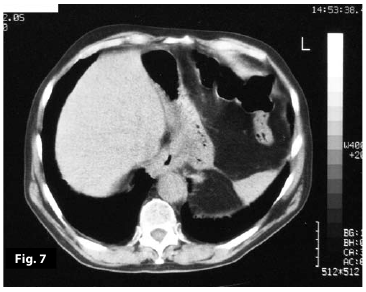

Figure5

Figure6

Figure5-6

Figure5-6-7-8